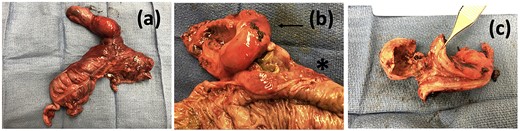

Operative specimen showing the segment of the colon resected with the fistula identified and the large enterolith extracted.

Case presentation # 1: An 80-year-old female with congestive heart failure and hypertension, presented to the emergency room with 4 days of diffuse abdominal pain associated with nausea, vomiting and anorexia. She was hemodynamically stable upon presentation, with upper abdominal tenderness on exam. Initial imaging (Figs 1 and 2) was obtained, showing a CCF with large bowel obstruction caused by an 8-cm gallstone in the descending colon. The patient was taken to the operating room for an exploratory laparotomy, where upon inspection a large gallstone in the descending colon and a fistulous communication between the gallbladder and hepatic flexure of the colon were noted. Takedown of the fistula was attempted, however because of extensive colonic involvement a decision was made to perform a right hemicolectomy with primary anastomosis, as well as a partial cholecystectomy at the level of infundibulum due to chronic inflammation and thickening of the gallbladder. The gallstone was taken out with the specimen (Fig. 3). The postoperative course was significant for exacerbation of heart failure, but ultimately, she was discharged home upon successful tolerance of a regular diet with return of bowel function.